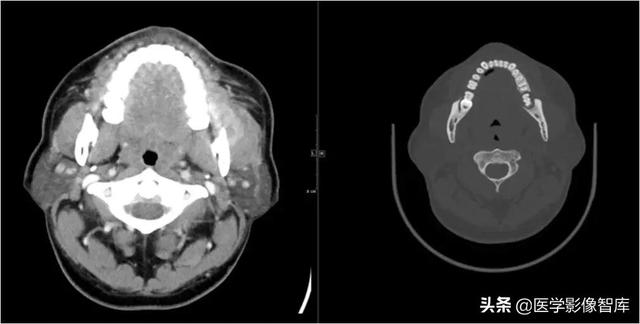

咀嚼肌间隙、颌下间隙、左侧颞下间隙,颊间隙,翼颌间隙

男,55岁,左下后牙反复肿疼1年余,加重1月余,疼痛剧烈伴张口受限,面部肿胀。

咀嚼肌间隙有脓肿形成。